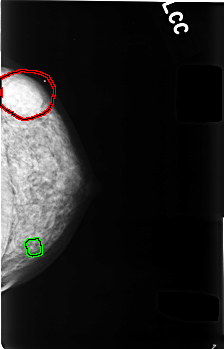

FILE: C_0480_1.LEFT_MLO.OVERLAY TOTAL_ABNORMALITIES 2 ABNORMALITY 1 LESION_TYPE MASS SHAPE ROUND MARGINS MICROLOBULATED ASSESSMENT 3 SUBTLETY 5 PATHOLOGY BENIGN TOTAL_OUTLINES 1 BOUNDARY ABNORMALITY 2 LESION_TYPE CALCIFICATION TYPE DYSTROPHIC DISTRIBUTION CLUSTERED ASSESSMENT 3 SUBTLETY 3 PATHOLOGY BENIGN TOTAL_OUTLINES 1 BOUNDARY |

FILE: C_0480_1.LEFT_CC.OVERLAY TOTAL_ABNORMALITIES 2 ABNORMALITY 1 LESION_TYPE MASS SHAPE ROUND MARGINS MICROLOBULATED ASSESSMENT 3 SUBTLETY 5 PATHOLOGY BENIGN TOTAL_OUTLINES 1 BOUNDARY ABNORMALITY 2 LESION_TYPE CALCIFICATION TYPE DYSTROPHIC DISTRIBUTION CLUSTERED ASSESSMENT 3 SUBTLETY 3 PATHOLOGY BENIGN TOTAL_OUTLINES 1 BOUNDARY |